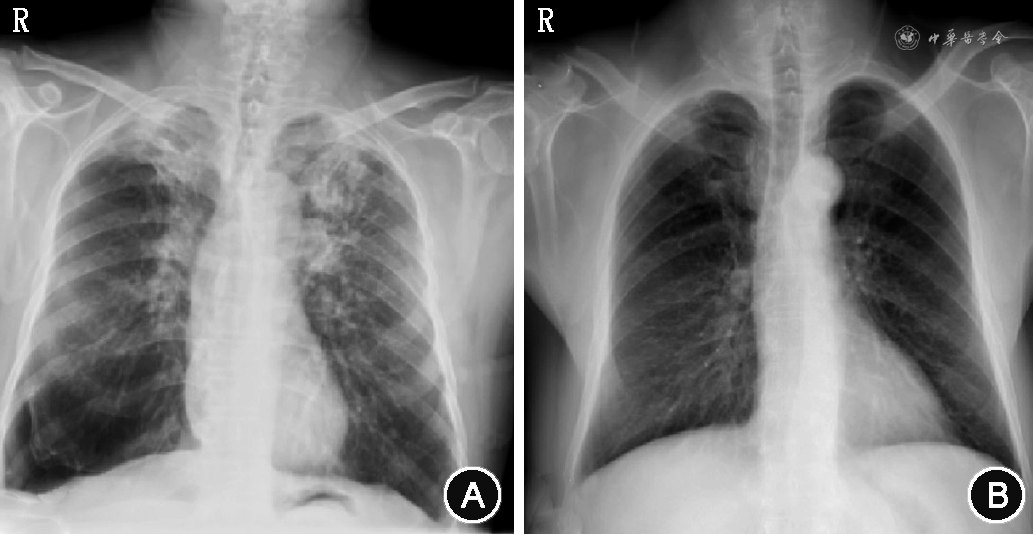

22例(66.7%)患者封堵成功,1例(3.0%)患者在术后1周内死亡,10例(30.3%)患者在行活瓣置入后未封堵成功(更换治疗方案或继续胸管引流)。治疗成功患者术前的胸管留置时间为(88.5±36.6)d,EBV治疗后胸管留置的时间为(29.6±11.4)d。EBV置入后成功取出的时间为(102.2±31.3)d。本研究EBV治疗的有效率为66.7%(22例),见图5。

32例患者术后随访6个月的并发症发生情况,活瓣分泌物附着29例(90.6%),轻度肉芽增殖13例(40.6%),中重度肉芽增殖5例(15.6%),活瓣移位或脱落1例(3.1%),出血1例(3.1%)。

近年来,EBV在BPF治疗中的应用逐渐增多,Tchkonia等[19]对30例BPF患者行EBV治疗,其中28例患者得到成功治疗。本课题组前期研究显示:EBV在胸外科术后BPF中的治疗成功率达73%,表明其有效性与临床价值[20]。本研究结果显示,EBV置入术治疗外周型BPF的有效率为66.7%(22例),治疗后胸管留置的时间较术前有所改善,且症状得到有效缓解。10例未封堵成功病例,考虑可能是局部封堵后形成局部或叶间新的侧支通气,造成封堵未能起效。本研究采用经支气管镜行EBV置入治疗BPF的严重并发症发生率低,且可以取出,具有可逆性,是一项安全性较高的治疗技术。EBV治疗胸外科术后支气管胸膜瘘和自发性气胸患者更适合活瓣置入,这取决于瘘管的长度和直径,一般标准是手术残端足够长,且瘘口直径为3~8 mm。如果术前评估出漏点过多或相邻肺叶间存在侧支通气,要考虑手术后肺功能的损失,再决定是否继续行封堵术。使用数字引流瓶和Chartis系统,是一种准确有效的漏点探查方法。本课题组在临床实践中发现,数字引流瓶对漏气的判断具有更高的敏感性,数值化的显示能更直观地表明患者漏气情况。因此首选数字引流瓶作为寻找漏点的工具。Chartis 系统受气流变化影响较大,对漏气量少的支气管敏感性不高,但是对于侧支通气的判断准确性高,所以两者同步使用,可显著提高封堵的成功率。另外,本研究发现利用单向活瓣的特点,对于远端支气管消化道瘘的,可以尝试反向置入EBV进行封堵治疗。目的是防止消化液反流入气道,以提供进一步手术机会。